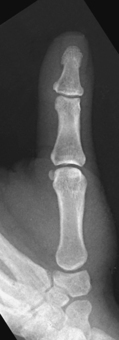

Structures shown: A PA projection of the appropriate digit is visualized (Figs. 4-16 through 4-19).

Structures shown: PA projections of the carpals, metacarpals, phalanges (except the thumb), interarticulations of the hand, and distal radius and ulna are shown in Fig. 4-54. This image also shows a PA oblique projection of the first digit.